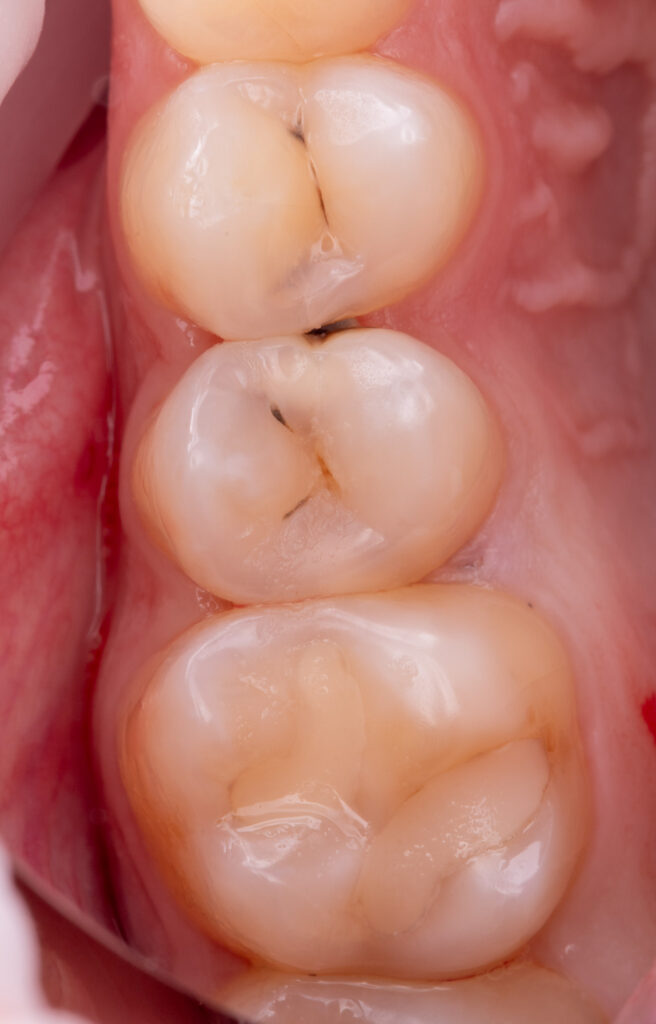

According to the anamnesis, a 23-year-old female patient presented with complaints of food impaction between teeth 2.5 and 2.4 and pain when consuming sweet foods.

The patient denied any episodes of nocturnal pain, which is considered a characteristic symptom of pulpitis.

Cold sensitivity testing confirmed pulp vitality, as the pain subsided within 3 seconds after removal of the cold stimulus.